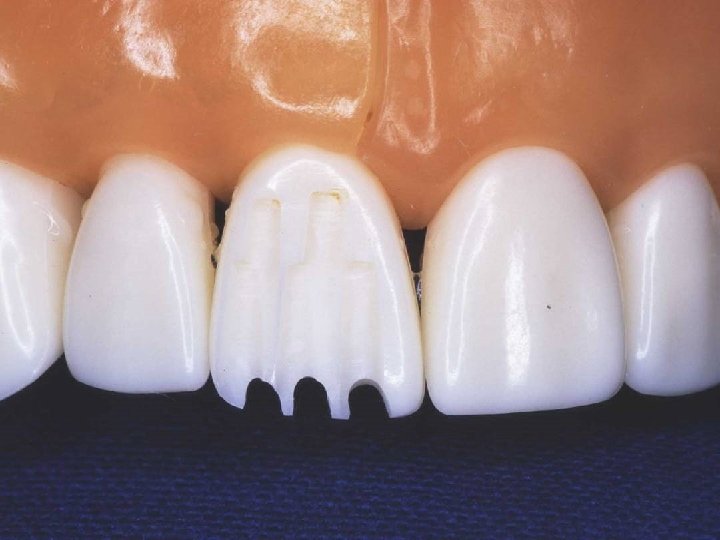

Depth-orientation grooves

Incisal reduction

Incisal facial reduction

Gingival facial reduction